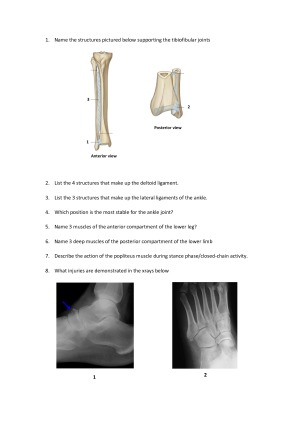

This practice exam was put together for the podiatry students I tutor. It includes a total of 94 short answer Q's based on the learning objectives from each lecture. Both anatomy and biomechanics content is included and an answer sheet provided.